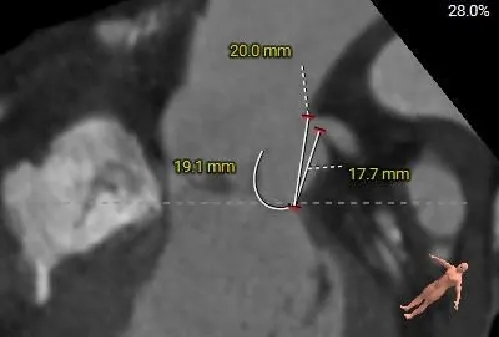

三叶式主动脉瓣,微量钙化,瓣叶增厚;瓣环周长折算直径26.6mm,LVOT29.3mm。

左冠开口高度约为17.6mm,右冠开口高度约为16.3mm,双侧冠脉堵塞风险较低。

左室增大,瓣环夹角54°,非横位心。